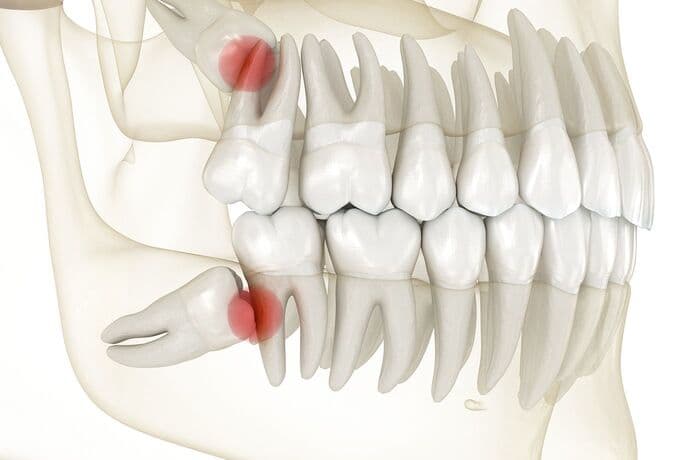

親知らずとは

親知らず(第三大臼歯)は、上下左右それぞれ一番奥に生える歯で、通常20歳前後に生えてくることが多いため、親が子供の歯の生え変わりを知らない時期に生えることから「親知らず」と呼ばれています。しかし、現代では顎の大きさや生活習慣の変化により、親知らずが正しく生えてこないケースが増えています。

「親知らず=最前方にある前歯から8本目の歯を親知らずと言います。古くは奥歯として普通に使われていましたが、食生活の変化によって現代人は顎が小さくなり、生えるスペースがなく横向きや斜めに生えるケースが増えたと言われています。正しく生えていない親知らずの多くは、手前の歯を押すなどして痛みの原因となったり歯並びの乱れを招いたりします。

親知らずが引き起こすトラブル

親知らずは必ずしも問題を引き起こすわけではありませんが、正常に生えてこない場合、以下のようなトラブルを招くことがあります。

- 隣の歯(第二大臼歯)への悪影響

- 斜めや横向きに生えてくる親知らずは、隣接する歯との間にプラークが停滞することで、虫歯や歯周病の原因となります。

状態が悪い場合は、隣接する歯と親知らずの2本の抜歯が必要なるケースがあります。 - 歯肉の腫れや炎症(智歯周囲炎)

- 親知らずの周囲にプラークが停滞することで、歯茎に炎症が起こることがあり、腫れや痛み、口臭を引き起こします。これを「智歯周囲炎(ちしししゅうえん)」と呼びます。

- 口腔内のスペース不足による歯列の乱れ

- 親知らずが無理に生えてくることで前方の歯が押され、歯並びが乱れる原因になることがあります。